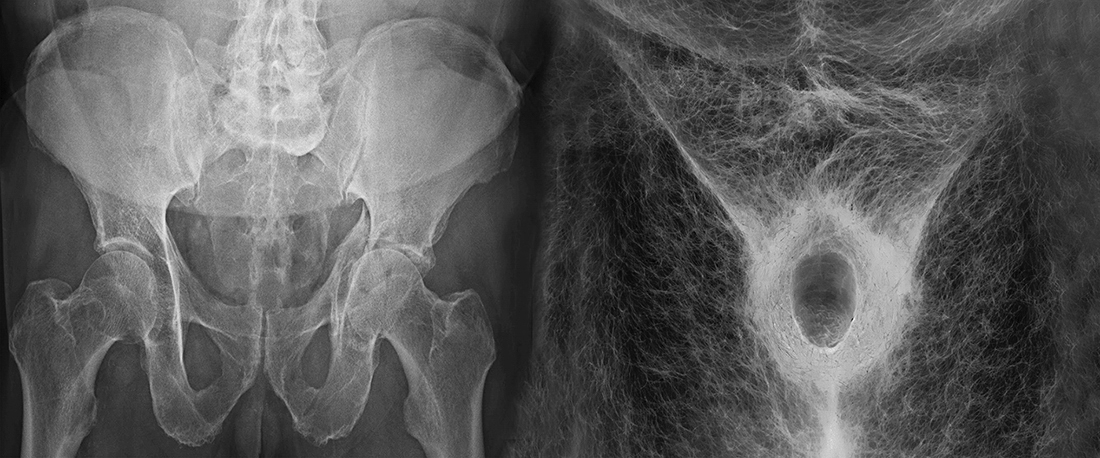

TITLE: WHAT YOU ARE, WE WERE

This work aims to recover the look and conceptions of ancient philosophy, which was promoted by the Capuchins and similarly many other cultures far from us, such as those of the ancient settlers of North America and Latin America: the assumption, in ourselves, of the reality of our death ("What we are, you will be").

With a look devoid of fears, almost analytical, the author studies, through his own body, his three states or realities: the external (epidermis), the internal, and the inevitable future that is to come (it is said that we started to die from the moment we are born) .